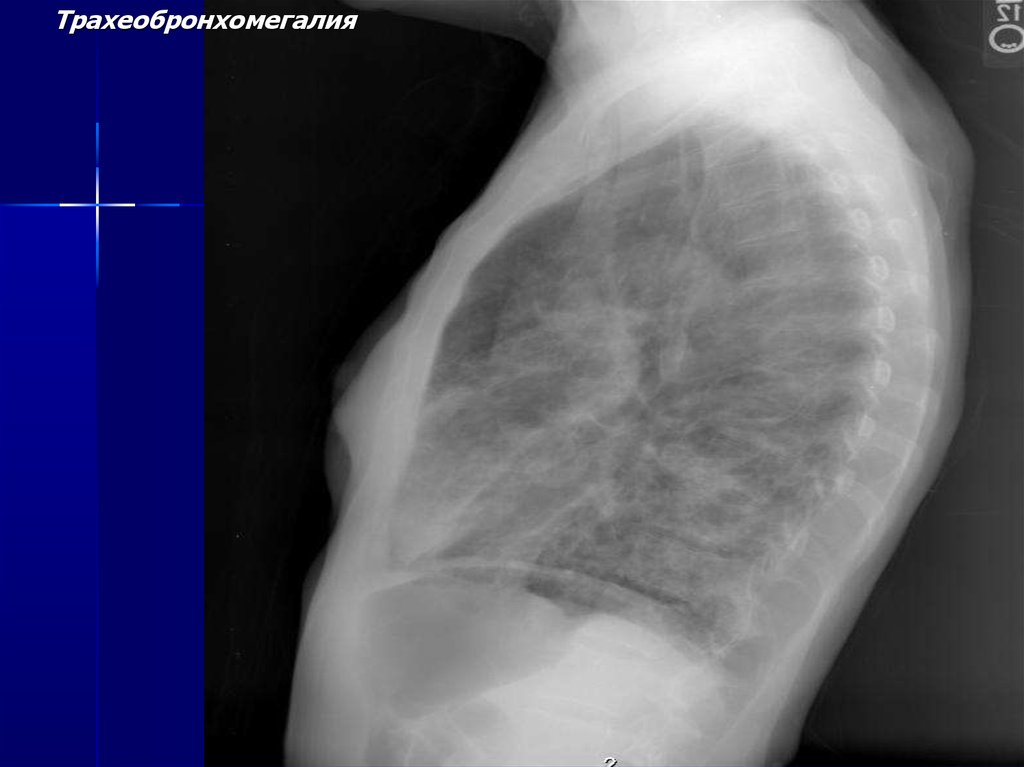

Трахеобронхомегалия